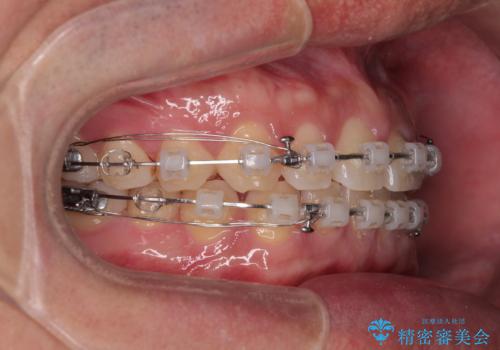

- クリアブラケット

- 1年7ヶ月

- 上下前歯の隙間を気にして来院された患者様です。

飲み込みや話をするときに舌を突出させる癖が強くあり、それが原因でスペースが空いていました。

舌癖を改善するためのトレーニングを行いながら、ワイヤー装置を用いて前歯の隙間を閉じていくこととしました。